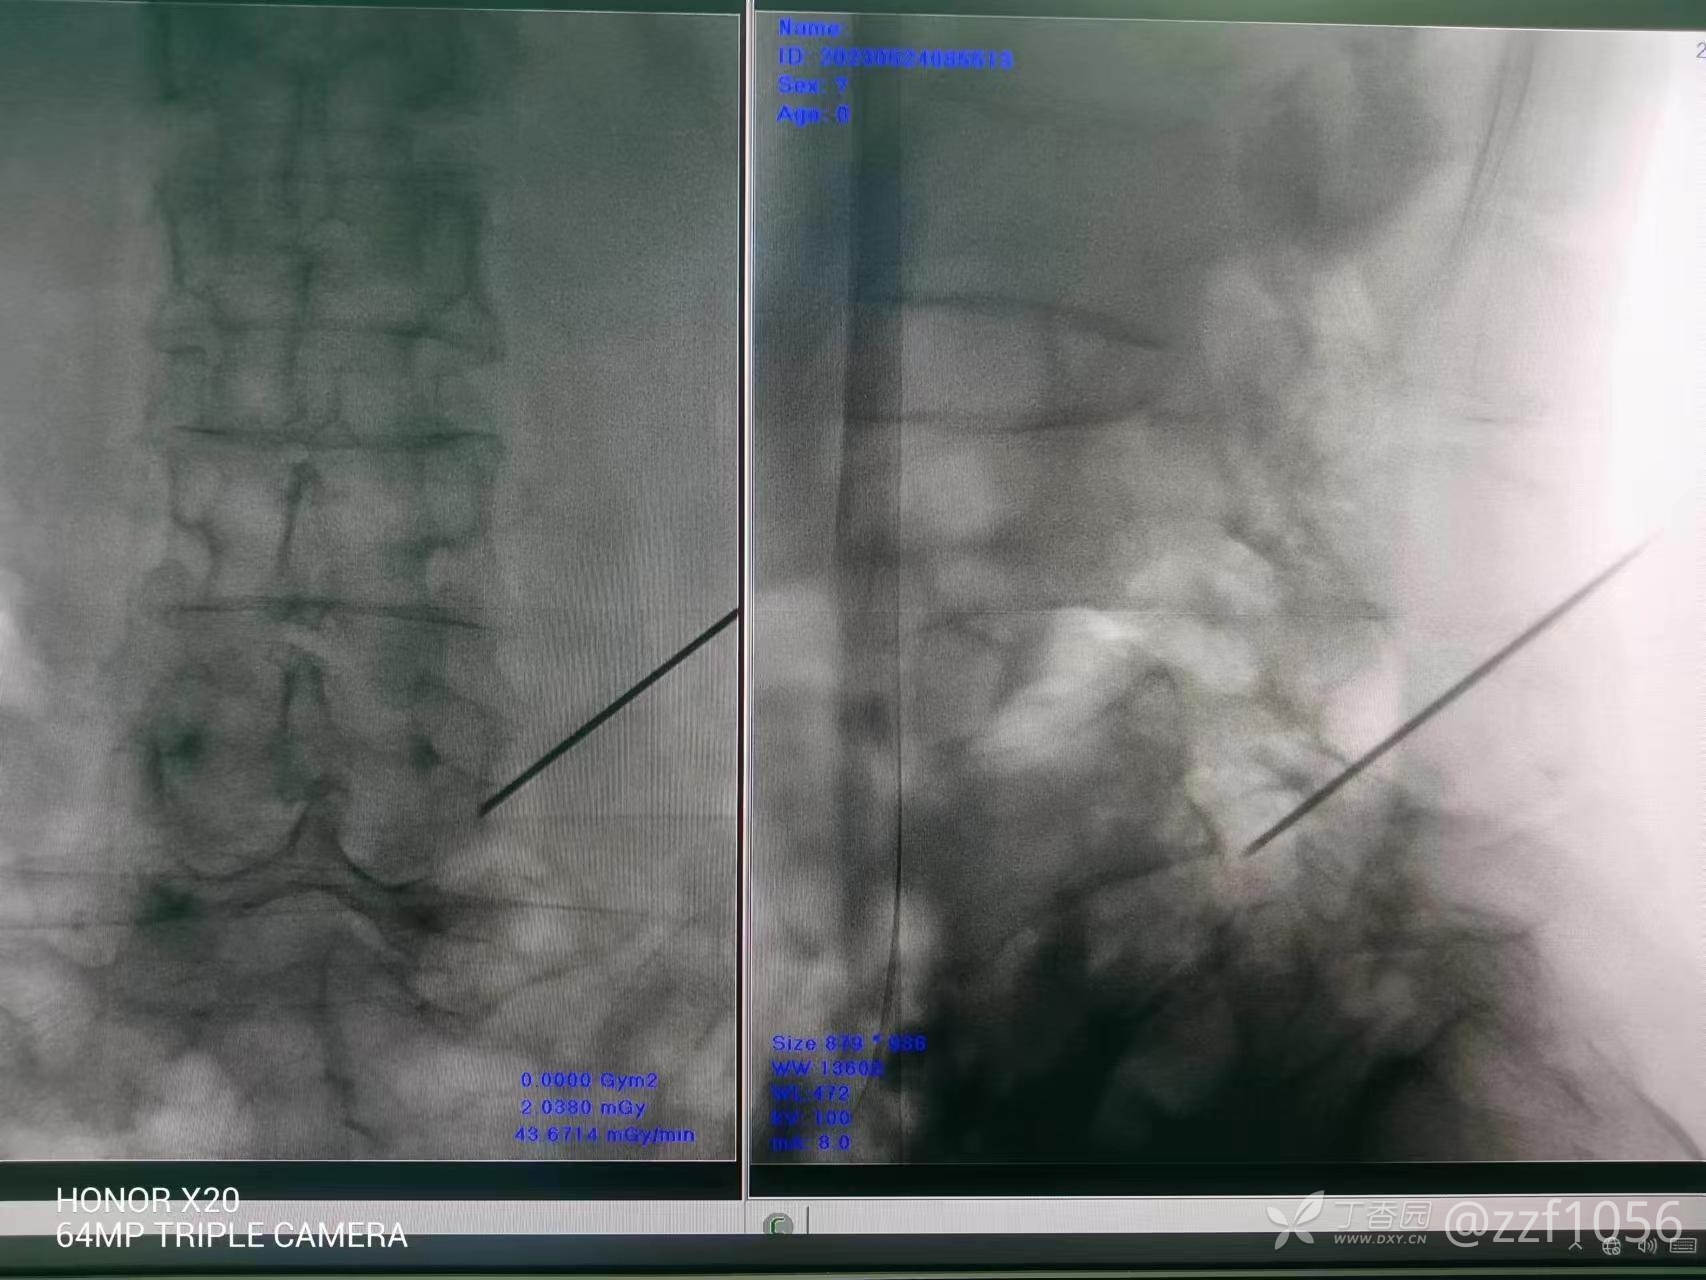

先阻滞L4/5

针尖靠外了,患者无法俯卧太长时间,稍微调整后用得宝松阻滞,阻滞后患者自诉稍好转,返回病房